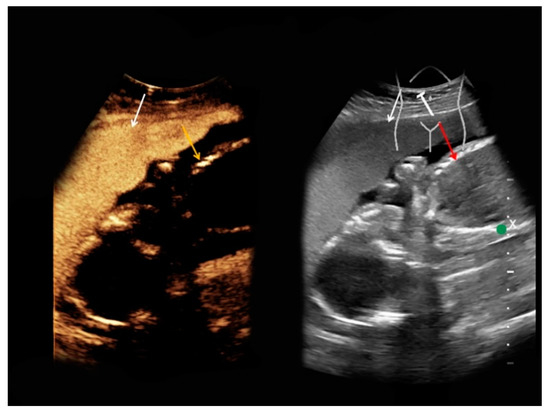

| #1 | 30 | 27 | Renal angiomyolipoma | B-mode: hypoechoic, 14 cm Doppler: no hypervascularization CEUS: rapid early contrast enhancement, slight late wash-out | T1-hypointense, T2-hypointense, restricted diffusion |